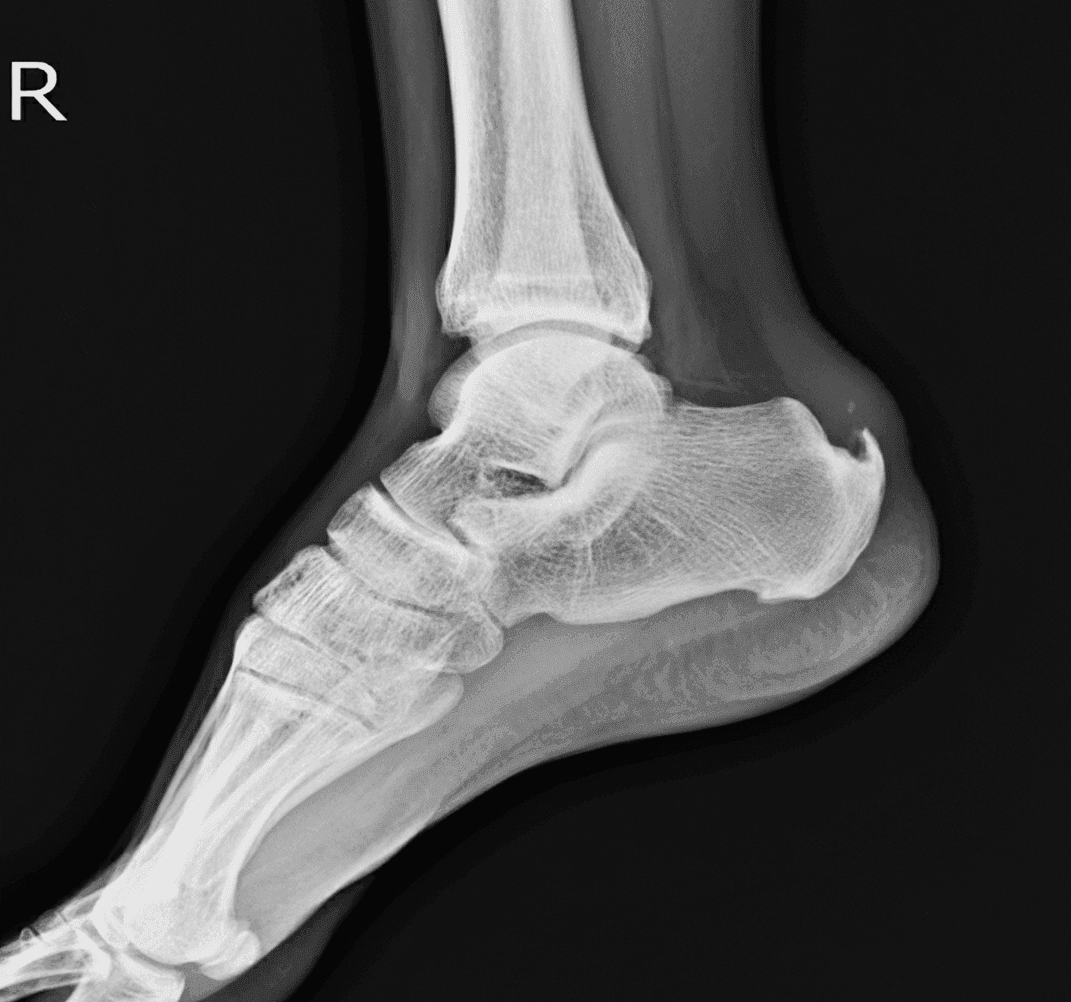

Ostroga piętowa, nazywana także entezopatią rozcięgna podeszwowego, to przewlekły stan przeciążeniowy w okolicy guza piętowego, związany z odkładaniem się złogów wapnia w najbardziej obciążanych fragmentach rozcięgna oraz tylnej części kości piętowej. Pojawiający się ból pięty wynika przede wszystkim z reakcji zapalnej w tkankach miękkich i postępującej degradacji rozcięgna, a dopiero w dalszym etapie z obecności samej narośli kostnej. Pacjenci często nie zdają sobie sprawy, że uporczywy, punktowy ból w okolicy pięty pojawia się jeszcze zanim widoczna będzie typowa narośl w badaniach obrazowych

Warto pamiętać, że nie każdy ból stopy w śródstopiu lub okolicy pięty oznacza od razu obecność ostrogi piętowej, dlatego konieczne jest prawidłowe rozpoznanie oparte na wywiadzie, badaniu przedmiotowym i diagnostyce obrazowej (USG, RTG).